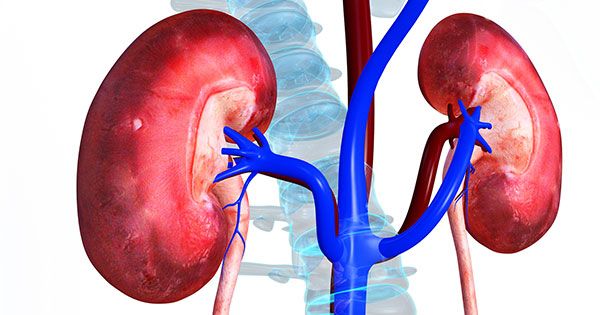

این علائم زنگ خطر از بین رفتن کلیه است

این علائم زنگ خطر از بین رفتن کلیه است بیماری کلیه ها در بدن خاموش بوده و تنها باتوجه کردن به برخی علائم مهم قابل تشخیص است و در صورت نادیده گرفتن این علائم به یکباره با خطر دیالیزی شدن یا از دست دادن کلیه مواجه می شوید.کلیه ها ارگان اصلی و مهم بدن بوده که وظیفه دفع مایعات و …